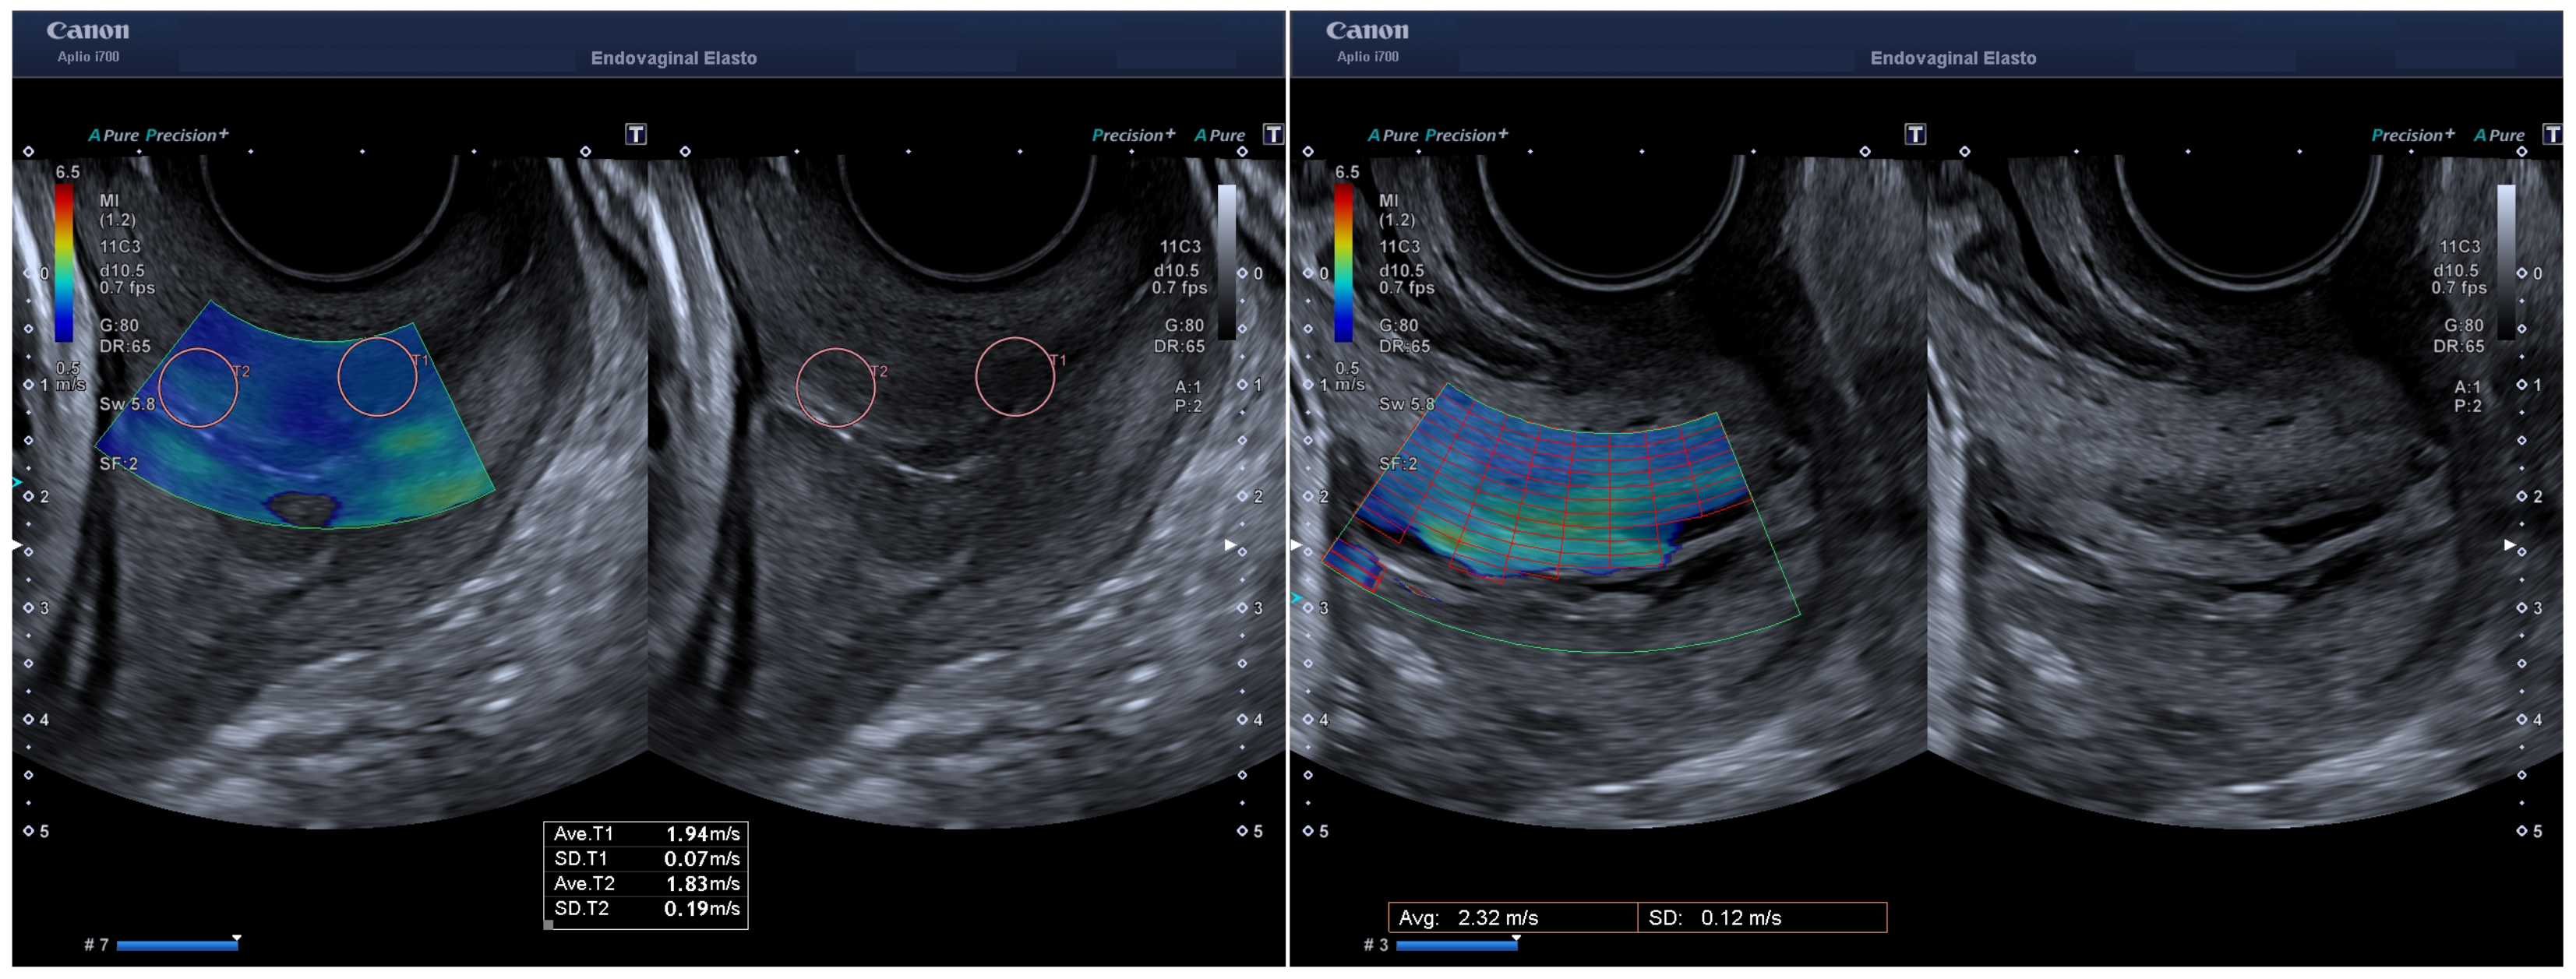

2.2. Cervical Evaluation